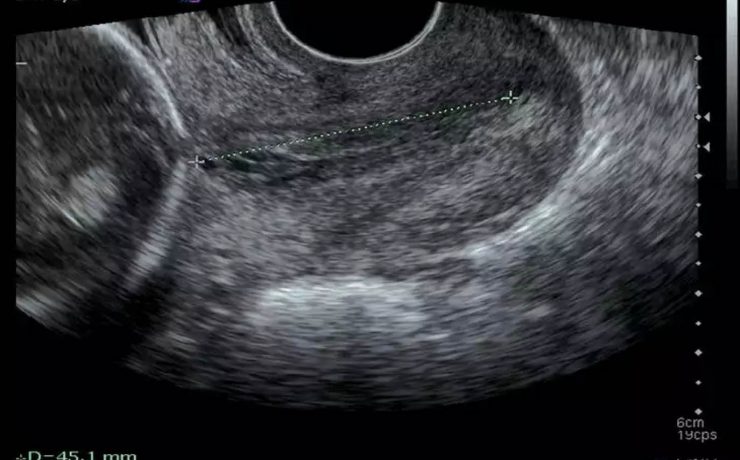

Alteraciones segundo trimestre de gestación.

Objetivo determinar la asociación entre ausencia e hipoplasia del hueso nasal fetal y alteraciones estructurales y/ o cromosómicas en el neonato, en la población en general en el ultrasonido del segundo trimestre. La gran mayoría de malformaciones congénitas no son prevenibles ya que constituyen accidentes en la organogénesis embrionaria y